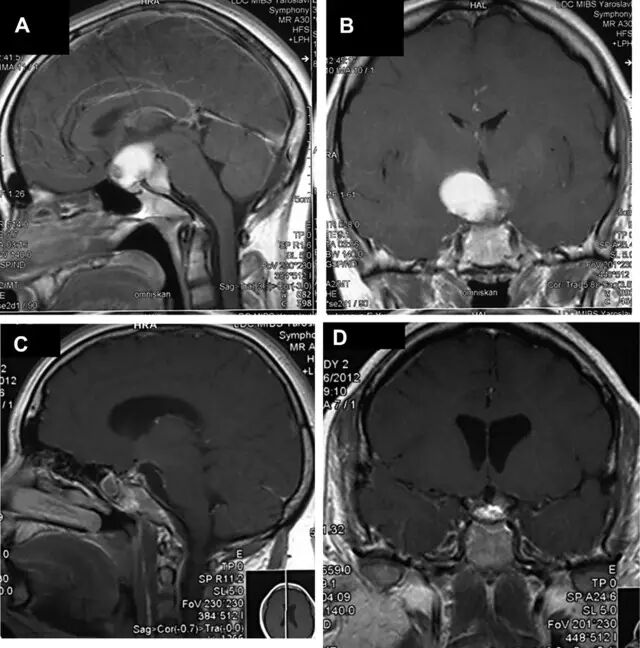

图 2 术前增强磁共振成像(A,B)显示脑室内外颅咽管瘤。术后矢状位(C)和冠状位(D)增强磁共振成像显示肿瘤完全切除